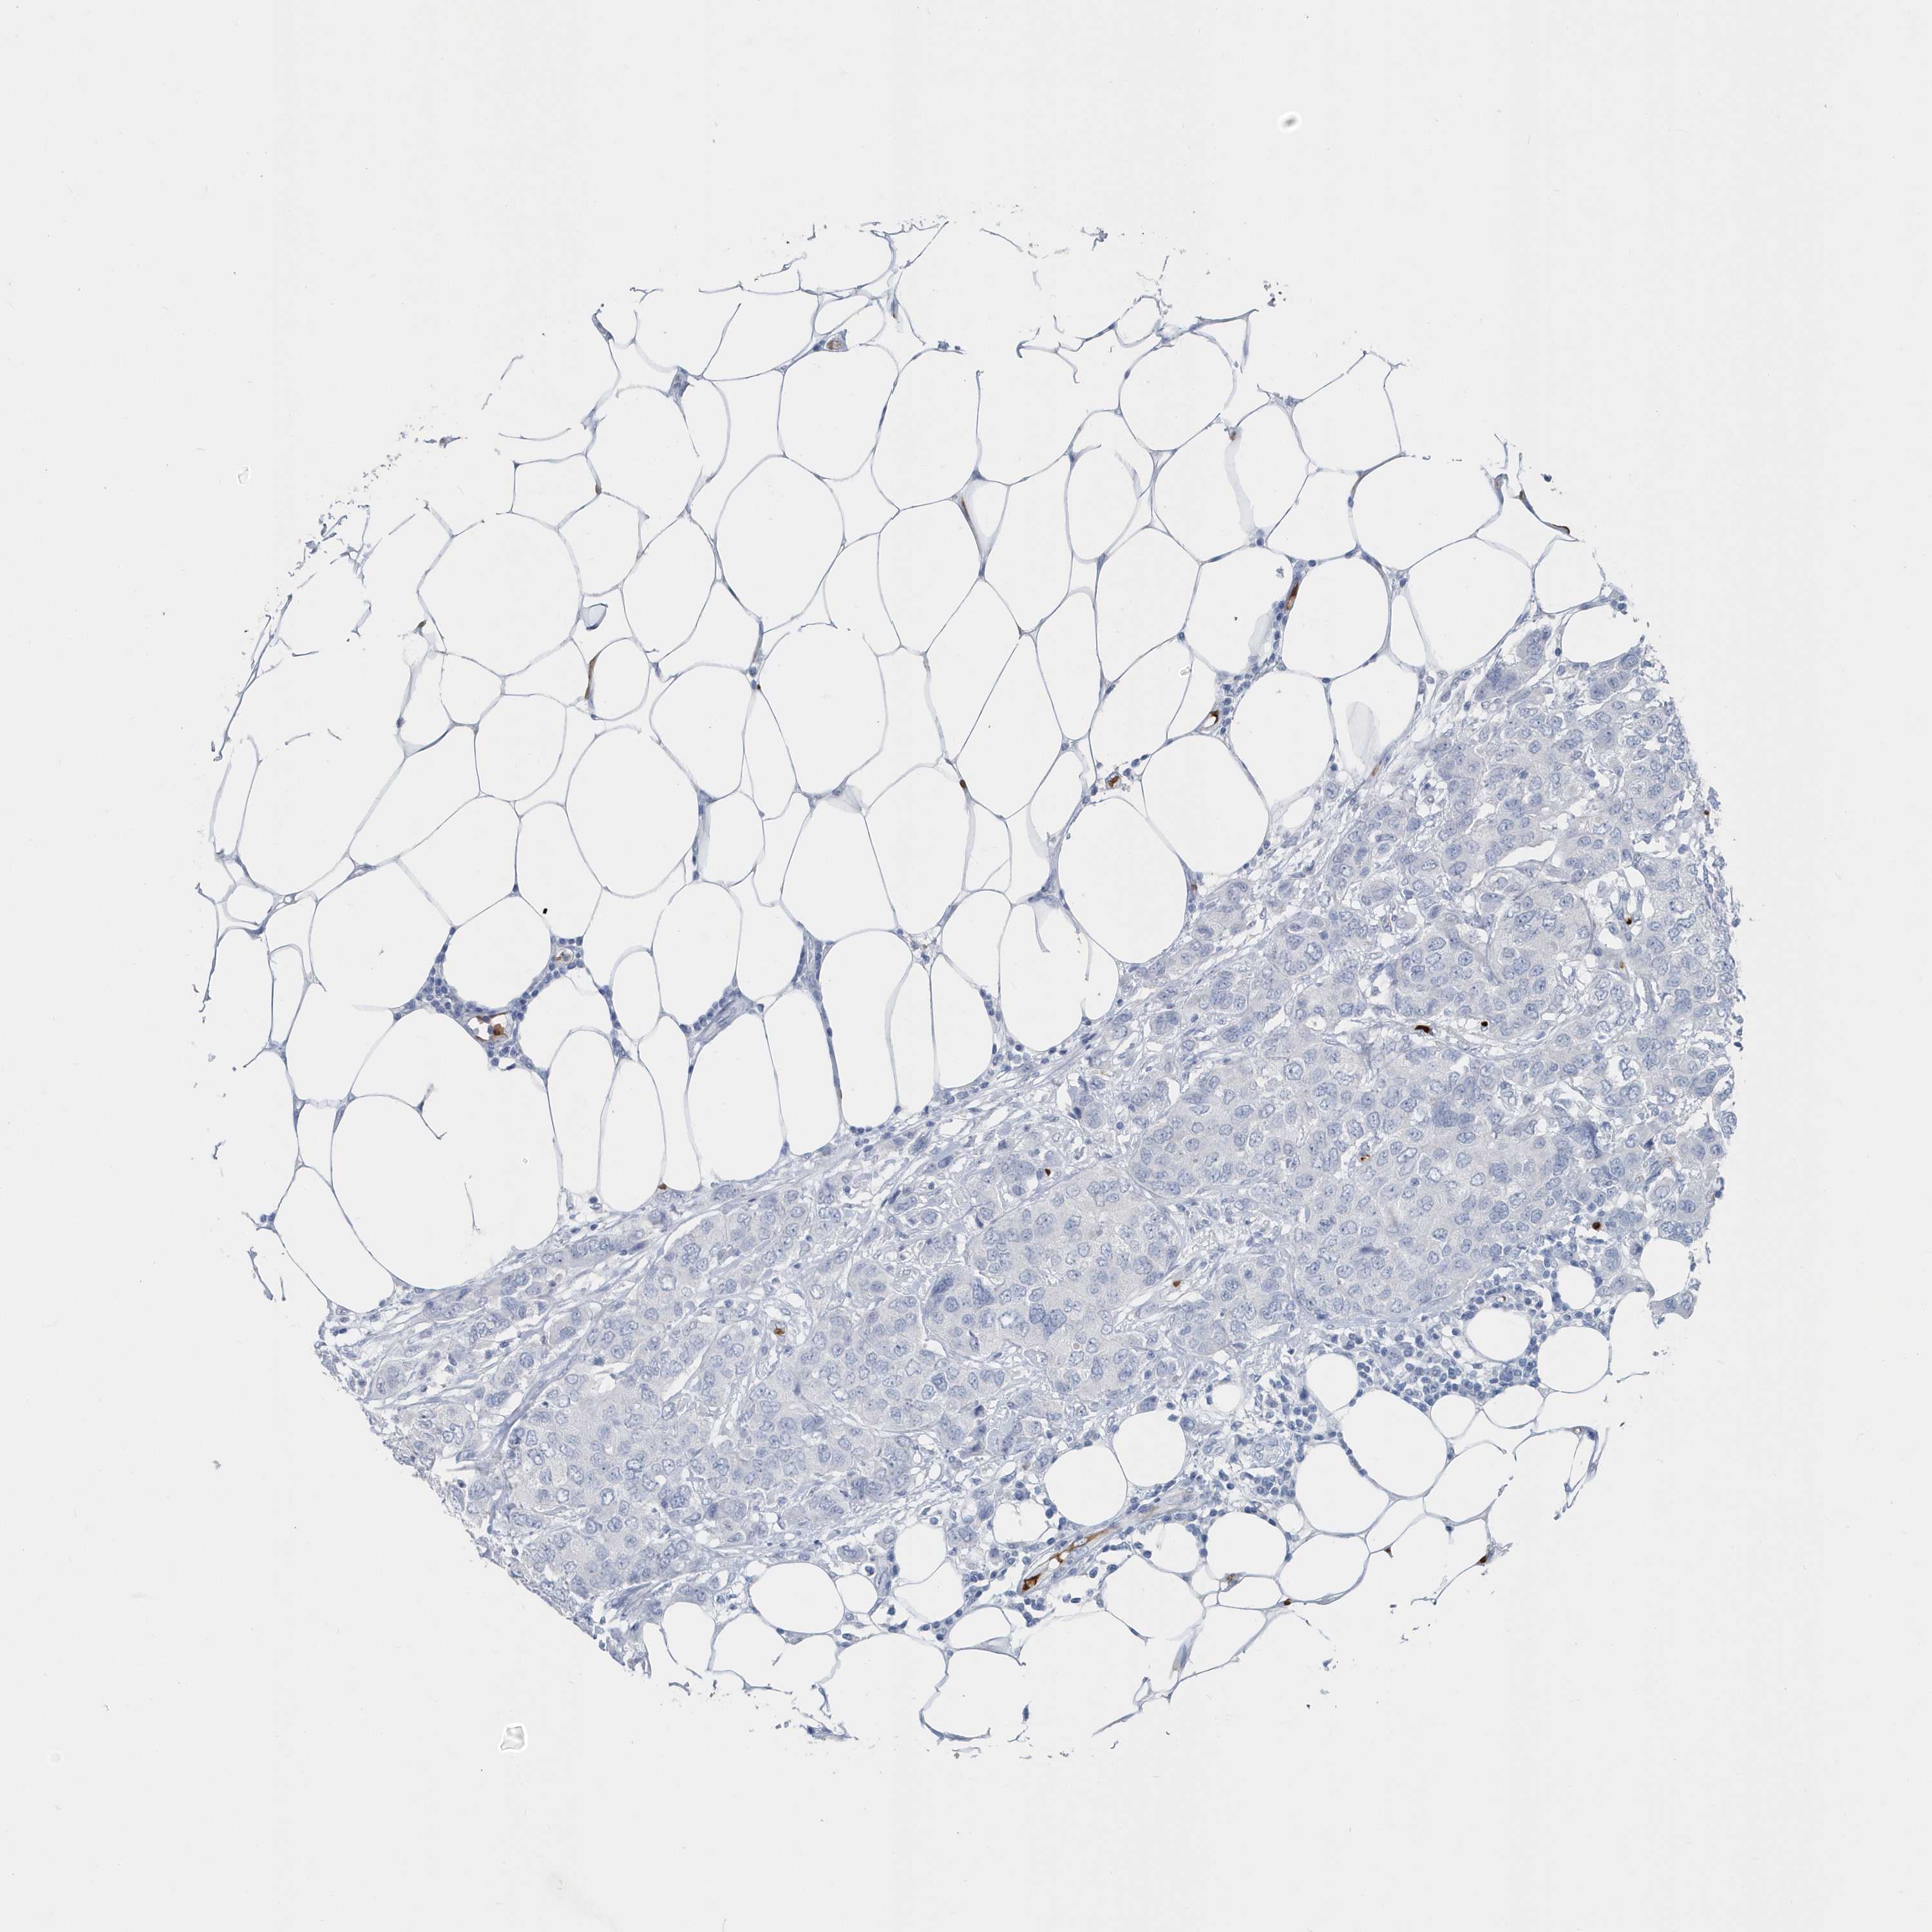

Breast cancer

Human cancer